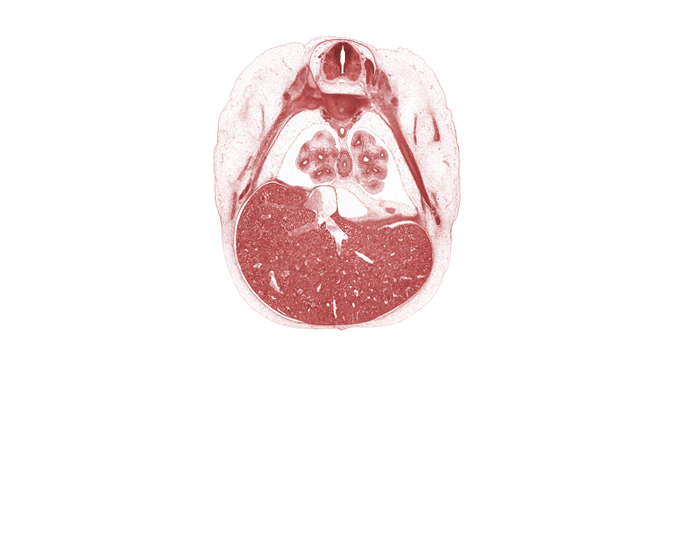

T-6 intercostal nerve, T-6 spinal ganglion, aorta, central canal, inferior vena cava, junction of efferent hepatic veins and inferior vena cava, lateral basal tertiary bronchus of right lung, left efferent hepatic vein, lingula of upper lobe of left lung, liver prominence, lower lobe of left lung, medial basal tertiary bronchus of right lung, oblique fissure, pulmogenic coat, rib 7, rib 8, right efferent hepatic vein, sympathetic trunk

Keywords: T-6 intercostal nerve, T-6 spinal ganglion, aorta, central canal, inferior vena cava, junction of efferent hepatic veins and inferior vena cava, lateral basal tertiary bronchus of right lung, left efferent hepatic vein, lingula of upper lobe of left lung, liver prominence, lower lobe of left lung, medial basal tertiary bronchus of right lung, oblique fissure, pulmogenic coat, rib 7, rib 8, right efferent hepatic vein, sympathetic trunk